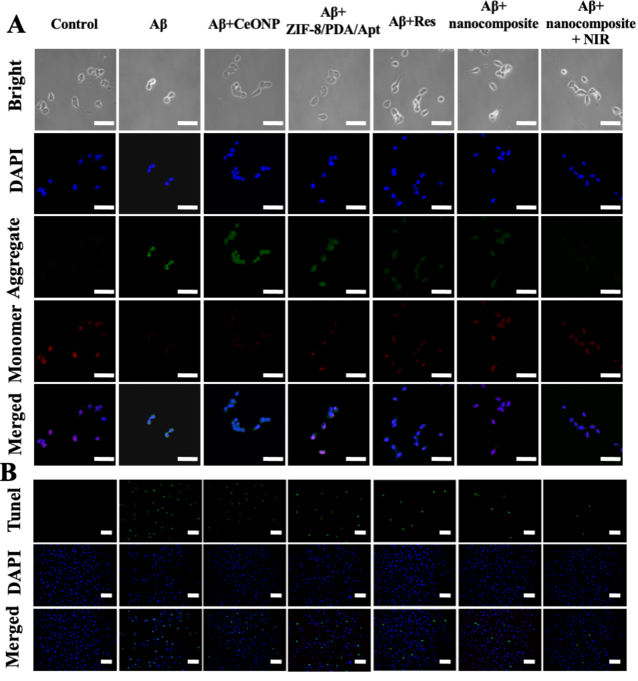

我們針對Aβ自聚集的現象,考察了該探針在抑制Aβ聚集以及解離原纖維方面的療效。ThT和TEM結果表明(圖四),探針既能夠抑制Aβ單體聚集,又能解聚Aβ原纖維,并且在光熱照射下,該性能能夠得到增強。細胞內治療結果表明,該探針能夠在細胞水平,有效抑制Aβ單體聚集,清除AβO誘導的細胞內過量ROS,并且探針的光熱性能,能夠增強其治療效果(圖五)。此外,JC-1、TUNEL以及Calcium-AM/PI染色結果均表明,該探針可以有效地保護神經細胞免于Aβ誘導產生的凋亡。

【圖五】探針在細胞水平的治療效果考察